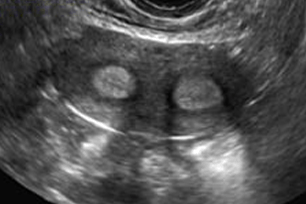

25yo P 0000 with the symptom of random intermenstrual bleeding, predictable q 25-day cycles with normal menstrual volume lasting 3 days, and primary infertility for 13 months. Day 18 transvaginal US shows an echogenic EEC of 12 mm, come central irregularity, and a possible septum involving the corpus. Sonohysterogram demonstrates two fundal polyps, one 8 mm long, the other 12 mm long.

37yo P-2002 with the symptom of heavy menstrual bleeding (HMB) for 18 months, a Hb of 10.5 and a ferritin of 13. You perform a transvaginal ultrasound and find a uterus that is 9 cm long with a central 2.5 cm mean diameter mass consistent with a leiomyoma. Sonohysterogram demonstrates a (FIGO Type 0, Type 1, Type 2, Type 3, Type 4) leiomyoma. She has a strong desire for future fertility.